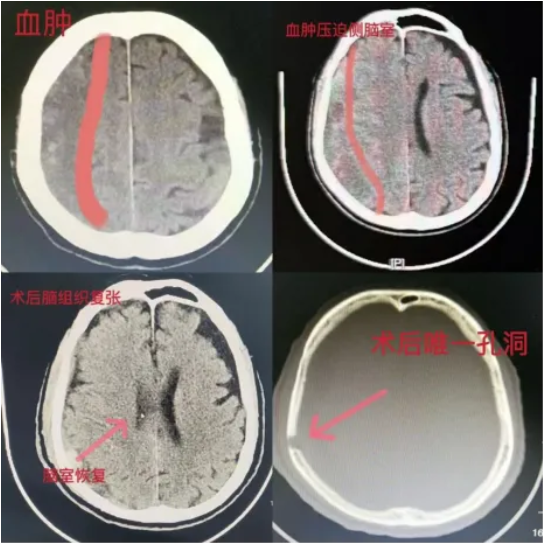

• 【健康科普】警惕老年人的沉默殺手,認識慢性硬膜下血腫

【健康科普】警惕老年人的沉默殺手,認識慢性硬膜下血腫

近日,臨滄市中醫醫院腦病科收治了一名72歲老年男性患者。當患者被轉送到我院急診科時,狀態很差,精神萎靡、言語遲鈍、無力,雙眼無神,嗜睡狀,不能坐立,更不能行走,...